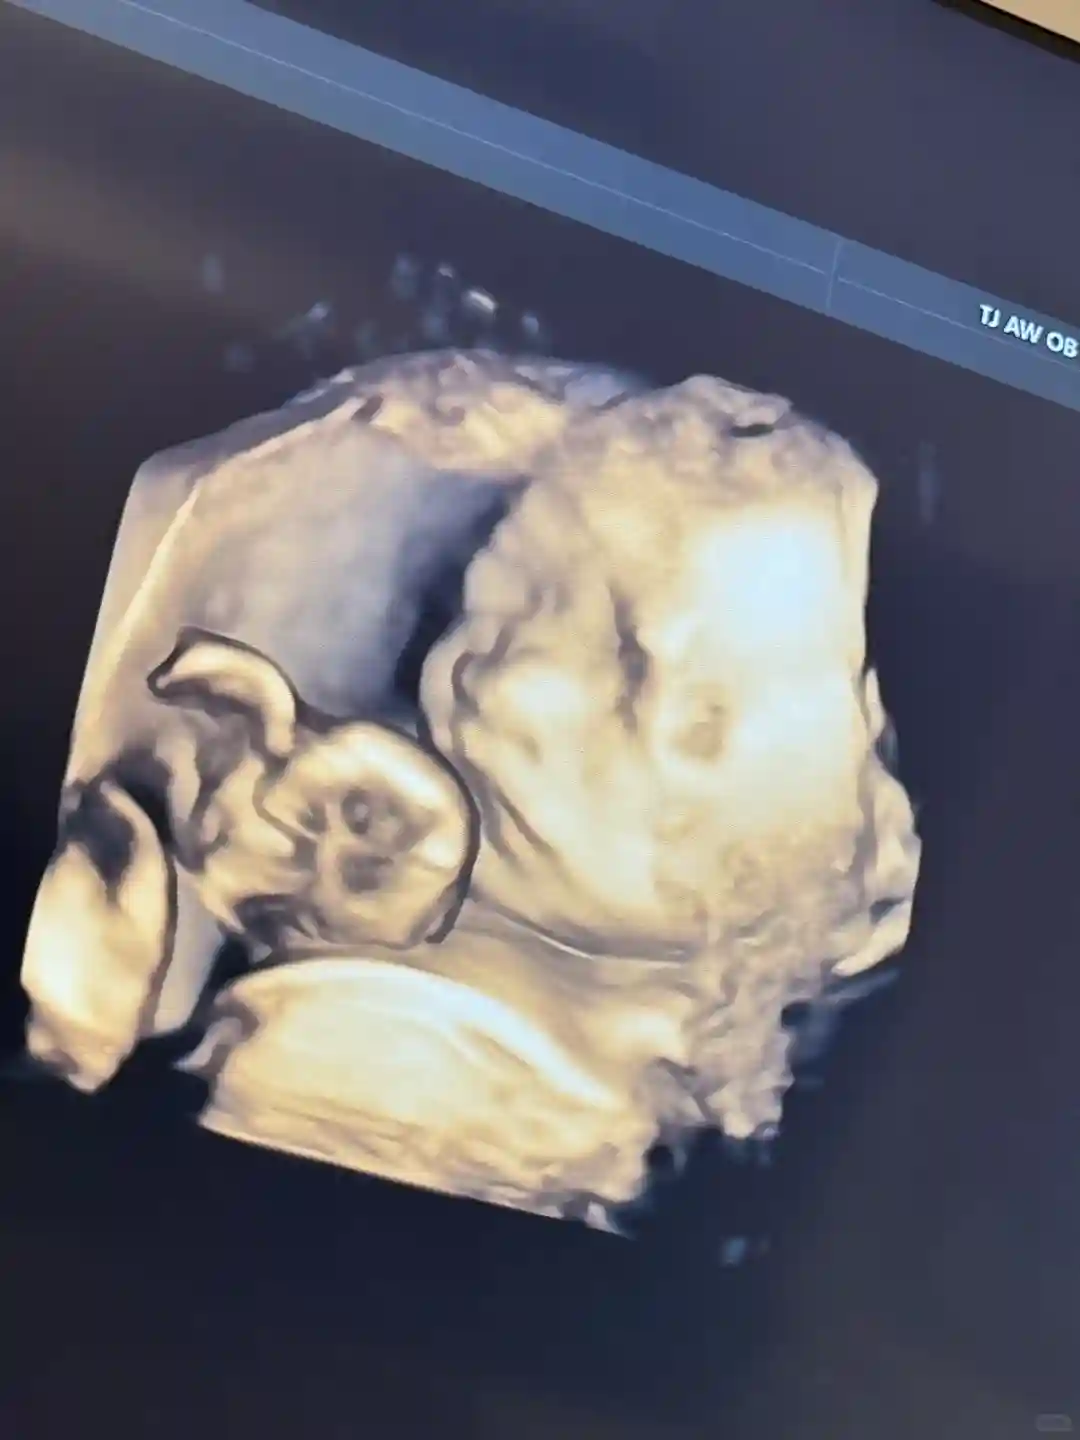

说起我做试管之路、感觉就跟做梦一样、从2023年春天开始、我才下了勇气开始决定做试管、第一次在我们市区做了4次、取了8个卵、配成5个、第一次移植1个鲜胚、生化了、我不甘心一直还在继续、第二次第三次各移植一个囊胚都没着床、好的胚胎已经用完了、就剩下两个4BC的了、第四次全部移植了、但是希望还是很渺茫、我每次都特别焦虑、有时候自己偷偷的哭、为啥就是不着床、我也找了各种原因、宫腔镜、免疫全部都查了、一点问题也没有、我当时都崩溃了、最后决定放弃了、从新换一家医院、我以前听说过天津爱维医院有套餐、他们都是包成功的、于是我从网上找到他们的电话、随后就跟他们那里的前台联系了套餐的过程、感觉挺好、最起码不用担心自己的钱白搭了、对自己也有了保障、2024年的大年初二、我老公我俩开车就来到了爱维医院、感觉他们这里服务态度真的特别好、我就下了决定就在这里做、当天我把所有的检查都从新查了一遍、过了没多久就准备促排、我的卵泡涨的有点慢、纪主任让我做理疗、做了几次理疗卵泡涨的还是不错的、11天就开始取卵、居然取了18个、出乎我的意料、最后配成了10个、纪主任让我全部养囊了、最后养成了5个囊、爱维医院对养囊的要求特别高、4BB就是挺不错的囊胚了、他们实验室特别厉害、后来我移植了一个4BB的囊胚、第八天让我验孕、我在家里整整呆了8天、第八天验孕再一次失败、根本就没有血值、我又一次崩溃了、但是我做的套餐、我也没有放弃、继续准备第二次移植、中间我又查了一下免疫、后来我又找到了保胎科的牛主任、她说我的免疫有点问题、让我提前一个月吃药、打针、我听了牛主任的准备了第二次移植、但是准备移植那天内膜不是特别好、才7.1、牛主任告诉我不用再在意内膜、内膜薄不一定会影响成功、牛主任又给了我希望、2024年6月24号、我准备了第二次移植、移植当天我问了纪主任、移植后可不可以上班、纪主任告诉我该干啥就干啥、不用太在意、也不用去想这个事、我听了纪主任的话、第二天就上班了、每天骑着电动车上下班、每天工作12个多小时、这次我是12天返院验孕的、当验血结果出来的那一刻、我都心慌不敢去看、当我打开手机看结果的时候我真的怕特别激动、血值328、我高兴的不得了、第一时间告诉我老公了、我老公也不敢相信、真的太高兴了、是爱维给了我希望、我现在已经6个月了、一路绿灯、感谢爱维医院~#天津爱维医院 #天津爱维保胎